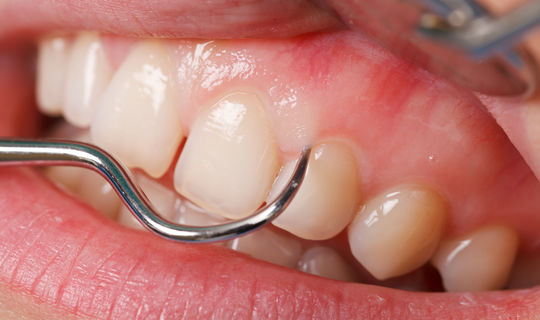

Parodontitin əsas əlamətləri bunlardır:

- Diş ətində şişkinlik və qızartı

- Diş ətində qanamağa meyllilik

Parodontitin müalicəsi bu sahənin mütəxəssisi tərəfindən həyata keçirilməlidir. Diaqnozun təyin olunması, ağırlıq dərəcəsinin müəyyən edilməsi və risk faktorlarının aşkar olunmasından sonra müalicə prosesi həyata keçirilir. Parodontitin müalicəsində konservativ, cərrahi və medikamentoz müdaxilə vasitələri müvafiq ardıcıllıq və ya kombinasiyada tətbiq edilir. Parodontitin müalicəsi çox zaman tək bir və ya bir neçə müdaxilənin icrası ilə məhdudlaşmayıb, pasiyentdən uzun bir dönəmi əhatə edəcək baxım, qayğı və qulluq tələb edir. Bunların pasiyent tərəfindən aparılması prinsipləri və instruksiyası xəstəliyin müalicəsini aparan parodontoloq tərəfindən verilir və müvafiq zaman intervalında nəzarətdə saxlanılır.